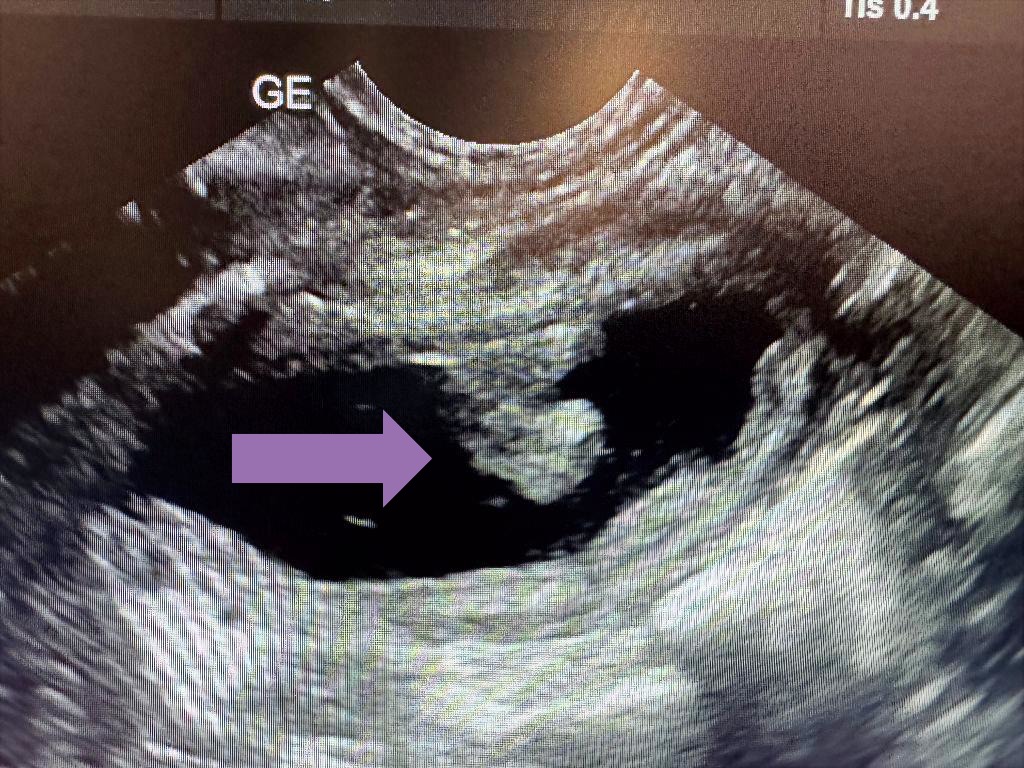

Ved den kliniske undersøkelsen fant vi ingen tydelige ytre funn som kunne forklare Aryas symptomer. Som neste steg valgte vi derfor å gjøre en ultralydundersøkelse av både urinblæren og livmoren. Livmoren var helt normal og kunne utelukkes som årsak til problemene.

I urinblæren derimot oppdaget vi en utvekst som ikke skulle være der. På ultralyd ser urinen svart ut, mens blæreveggen fremstår grå. Utveksten var tydelig synlig og ga mistanke om en alvorligere underliggende årsak.

Noen uker senere kom Arya tilbake for kontroll med ny ultralydundersøkelse av urinblæren. Både eiere og veterinærer var svært spente på resultatet. Gleden var stor da vi ikke lenger kunne se utveksten i urinblæren. Behandlingen hadde hatt bedre effekt enn forventet, og Arya kunne friskmeldes.